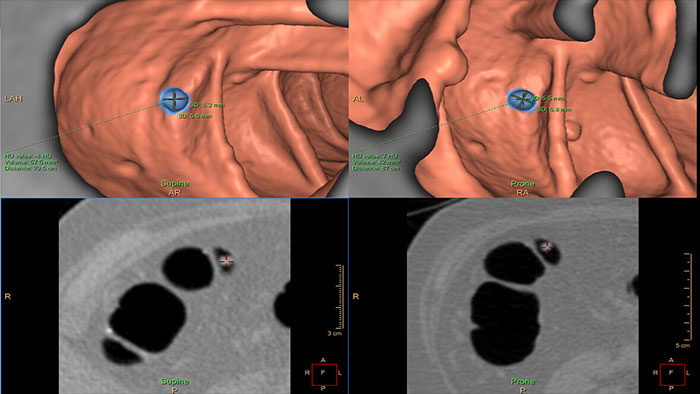

Virtual Colonoscopy

CT Virtual Colonoscopy

Reducing reading times in virtual colonoscopy

Enables 3D visualization of colon scans. The application automatically segments the air-filled colon and displays a calculated navigation path. The Perspective Filet view provides a synchronized display of the full colon surface wall with a single unidirectional view, reducing the need to review in both directions.

Benefits

• The Electronic Cleansing function can reduce the effect of residual liquids and fecal materials by "tagging" them via contrast-enhancement, allowing the user to automatically segment and subtract them.

• The CAD option* can be used as a second reader and assist in the search for polyps.

* CAD functionality is not available for sale in the USA.